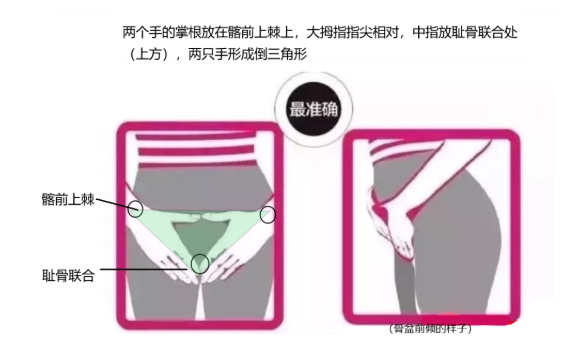

测试盆骨的两种方法:方法一:(这个方法更准)

方法二: